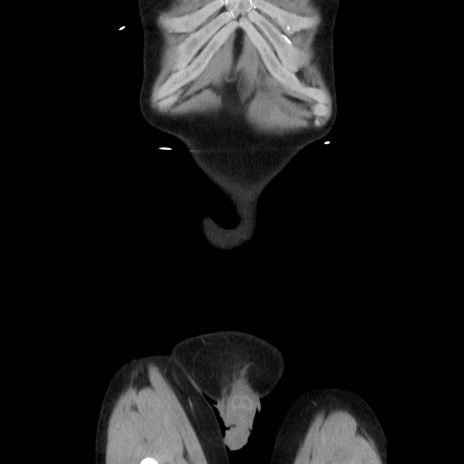

症例37(冠状断像)

横断像